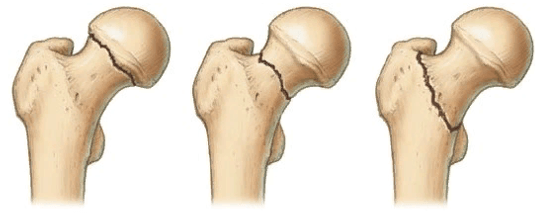

в. разные типы переломов шейки бедренной кости — схематическое изображение

В ортопедии и травматологии используют несколько классификаций переломов шейки бедра. Разные виды переломов имеют совершенно различный прогноз. К примеру, у людей младше 50 лет трансцервикальные переломы с углом менее 30 градусов срастаются относительно хорошо. У лиц более старшей возрастной категории субкапитальные повреждения и переломы с углом более 50 градусов срастаются крайне тяжело и имеют неблагоприятный прогноз.

Слева-направо: субкапитальный, трансцервикальный, базисцервикальный переломы.

- Субкапитальный. Располагается на границе между головкой и шейкой бедренной кости. Наименее благоприятный прогноз.

- Трансцервикальный. Локализуется в наиболее уязвимом месте - в области шейки бедренной кости.

- Базисцервикальный. Находится в месте соединения шейки с телом бедренной кости. Срастается намного лучше, чем предыдущие два варианта.

Большое прогностическое значение имеет угол слома. При вертикальном положении существует большой риск смещения с последующим нарушением кровообращения в тканях бедренной кости. Такие переломы имеют наиболее неблагоприятный прогноз.